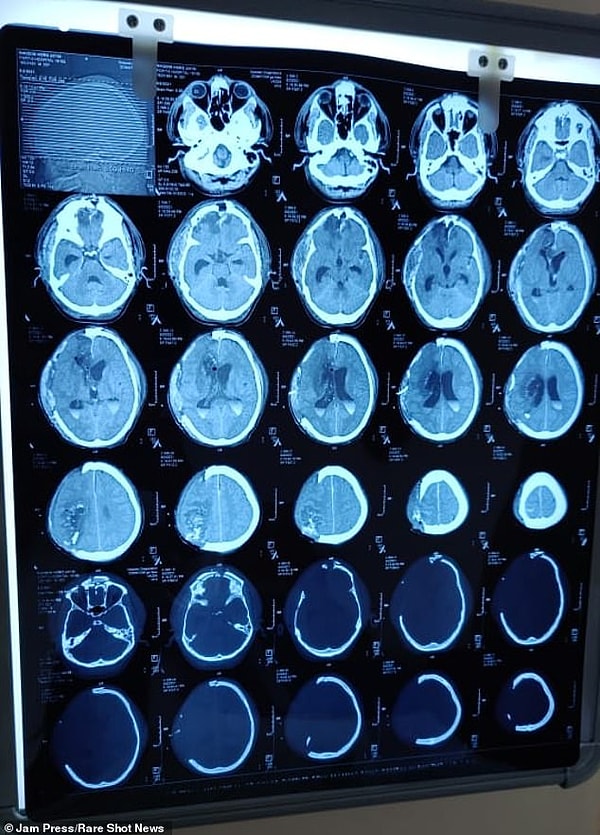

Коллеги-строители отрезали большую часть 6-метрового стержня перед тем, как отправить 24-летнего мужчину в больницу, где фотографии и рентгеновские снимки показали ужас всей ситуации.

Старший нейрохирург доктор Абхинав Гупта провел экстренную операцию, в ходе которой ему удалили большие части черепа, чтобы предотвратить дальнейшее повреждение мозга.

Гупта удалил части черепа 24-летнего парня и поместил их под подкожный мешок на животе - практика, используемая для сохранения жизнеспособности фрагмента черепа, которая позволяет мозгу набухать и облегчать приток крови к органу.